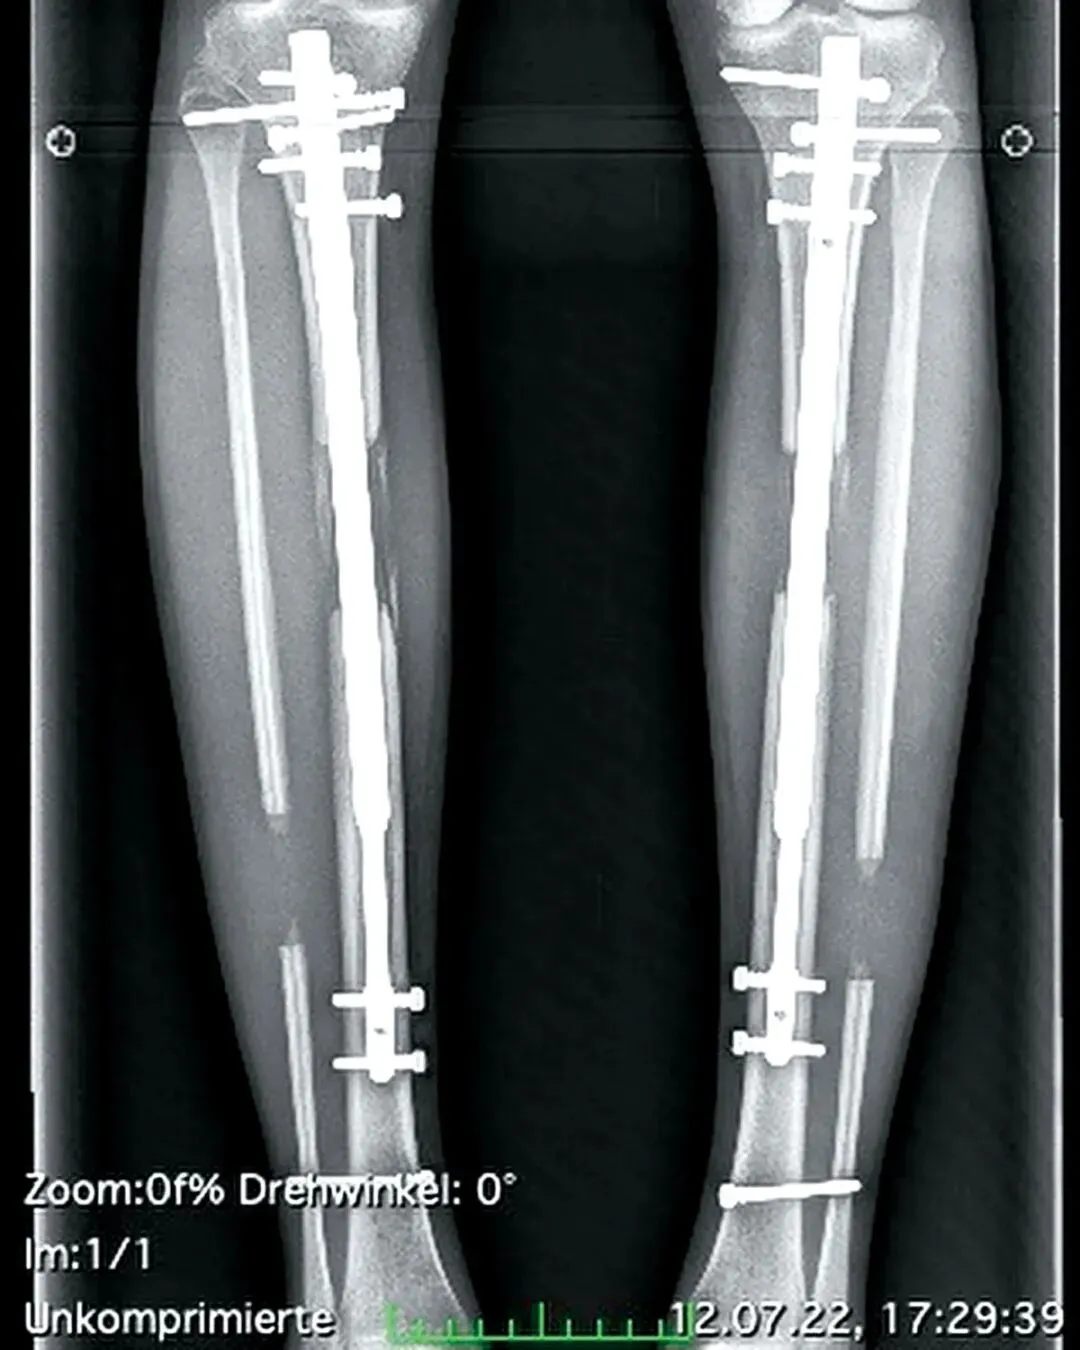

“断骨增高”手术的过程近乎残忍——胫骨被彻底截断,小腿肌肉被切开,每一个断点都插入了伸缩杆。除此之外,她还要花好几周的时间慢慢将自己的腿骨拉长。

她向德国《图片报》回忆手术增高的过程时依然心有余悸。腿骨插入伸缩杆后,特蕾西亚每天都要一点点旋转伸缩杆,增加骨头的间隙,整个过程要持续好几周。

◎ 德国模特特蕾西亚·费舍尔接受断骨增高手

24岁的时候,特蕾西亚接受了第一次肢体延长手术,将腿延长了3.3英寸(约8.4厘米);去年3月,这位模特又做了一次手术,将腿再延长2.1英寸(约5.3厘米)。两次手术的费用加起来超过12.8万英镑(约人民币115万元)。